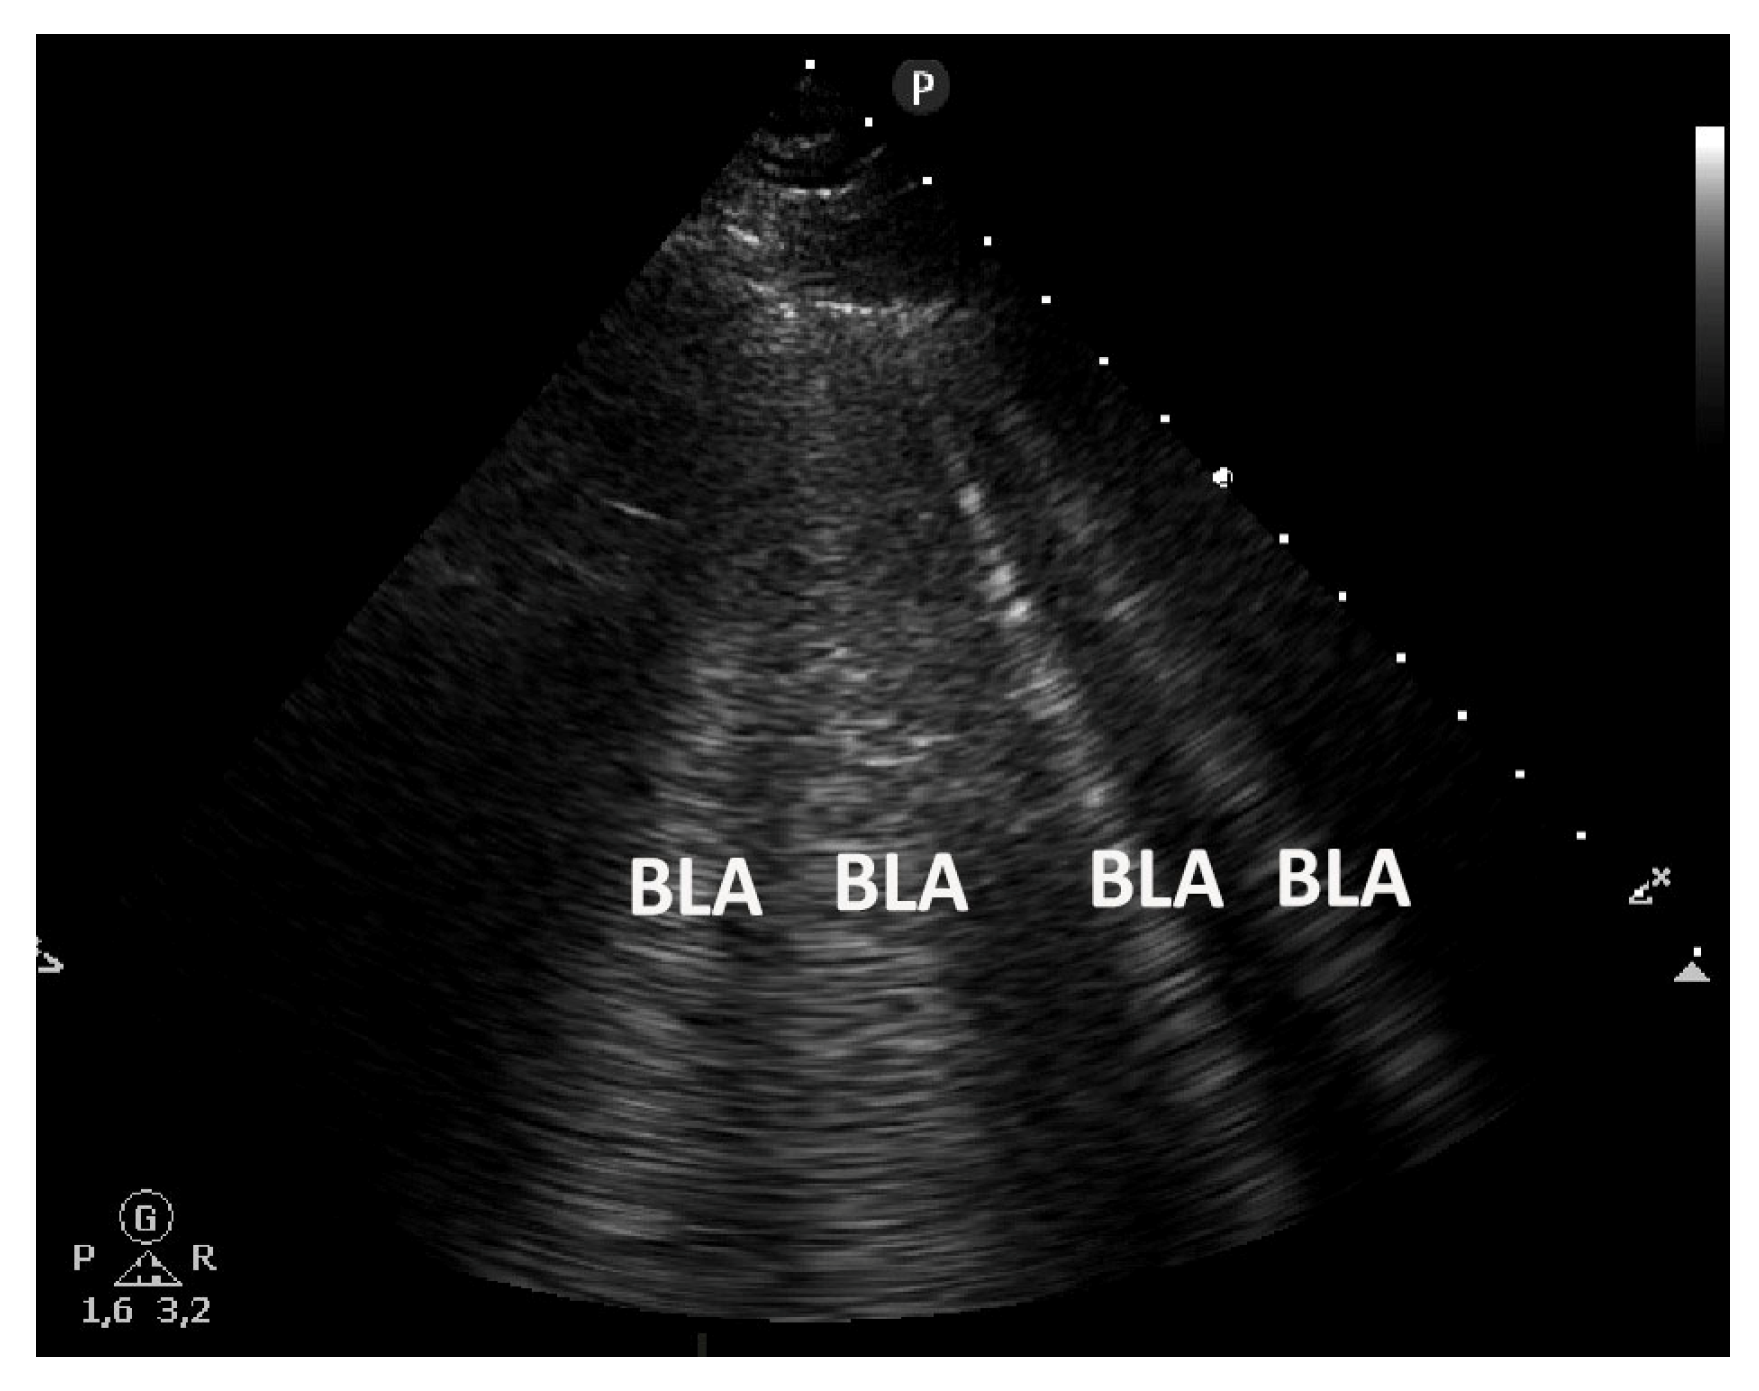

Figure 5.

A cardiogenic pulmonary edema shows multiple B-line artifacts (BLAs) homogeneously distributed (as a “curtain” of BLA in the center of the image and lateral as individual BLA) bilaterally (evaluated by convex low frequency transducer <5 MHz without interfering presets). They arise from a smooth pleural line, are well defined, hyperechoic, extending indefinitely (at least 10 cm), and moving with lung sliding.

Figure 6.

A cardiogenic pulmonary edema with multiple B lines (BLA) evaluated by sector transducer.